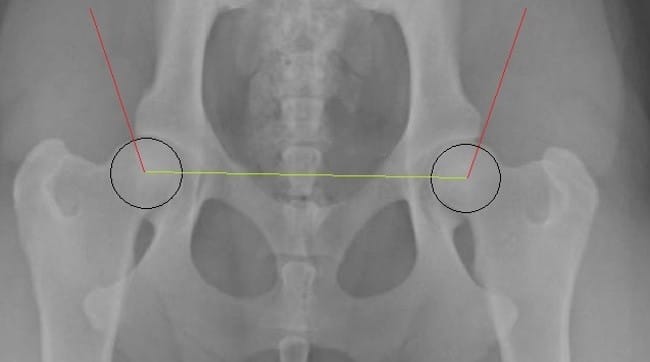

Je dois adopter une petite chienne cocker dans 2 mois. J’ai fait les démarches de réservation en envoyant un chèque qui s’avère être des Arrhes. Aujourd’hui une information supplémentaire s’est ajoutée sur le site de l’élevage concernant la mère des chiots, elle a une dysplasie de type C donc légère. Le père lui est de type B donc presque normal. C’est une maladie qui est héréditaire, par conséquent les chiots ont 50% de chance de présenter cette maladie.